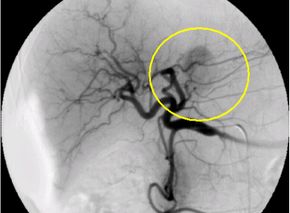

肝細胞がんに対する経カテーテル動脈化学塞栓療法の実際

大腿動脈(太ももの付け根の血管)又は上腕動脈の位置を確認し、消毒と局所麻酔を行い

ます。動脈を正確に穿刺してカテーテルを挿入し慎重に進めていきます。肝細胞がんを

栄養する血管が同定できたら、マイクロカテーテル(通常ものよりさらに細いカテーテル

)を栄養血管へ選択的に挿入し、腫瘍の近傍まで進め、そこから造影を行います。

次に肝細胞がんの径、腫瘍濃染、患者さまの全身状態、肝臓機能などを総合的に判断し

、マイクロカテーテルか治療後の造影では塞栓物質により肝細胞がんへの血流がなくな

っているので腫瘍は描出されません。

肝細胞がんを栄養する血管描出(塞栓前) 肝細胞がんを栄養する血管描出(塞栓後)

選択的動脈造影 上腸間膜動脈造影